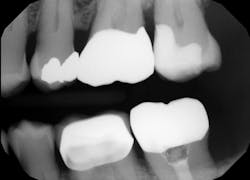

The lower left second molar was prepared for a class II composite restoration (figure 3). A sectional matrix band was placed and wedged. The preparation was etched, and adhesive was placed and cured. The VisCalor bulk was heated in the heating gun and then dispensed into the base of the box while in its flowable state. Note the complete adaptation of the material to the walls ofEditor's note: This article appeared in the November 2021 print edition of Dental Economics.